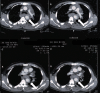

Background: We report a case of delayed endovascular correction of graft collapse occurred after emergent Thoracic Endovascular Aortic Repair (TEVAR) for traumatic aortic isthmus rupture.

Case presentation: In 7th post-operative day after emergent TEVAR for traumatic aortic isthmus rupture (Gore TAG® 28-150), a partial collapse of the endoprosthesis at the descending tract occurred, with no signs of visceral ischemia. Considering patient's clinical conditions, the graft collapse wasn't treated at that time. When general conditions allowed reintervention, the patient refused any new treatment, so he was discharged.Four months later the patient complained of severe gluteal and sural claudication, erectile disfunction and abdominal angina; endovascular correction was performed. At 18 months the graft was still patent.